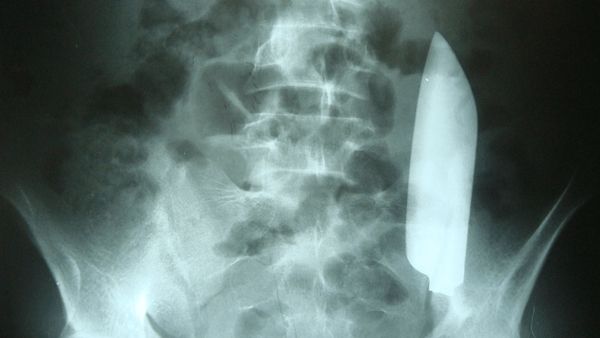

Preman Kampung di Ogan Ilir Ngaku Bercanda Ancam Korbannya Pakai Pisau

Tersangka Deni (25) ditangkap setelah mengancam petugas satpam dengan pisau. Dia mengaku hanya bergurau, namun kini menyesali perbuatannya.